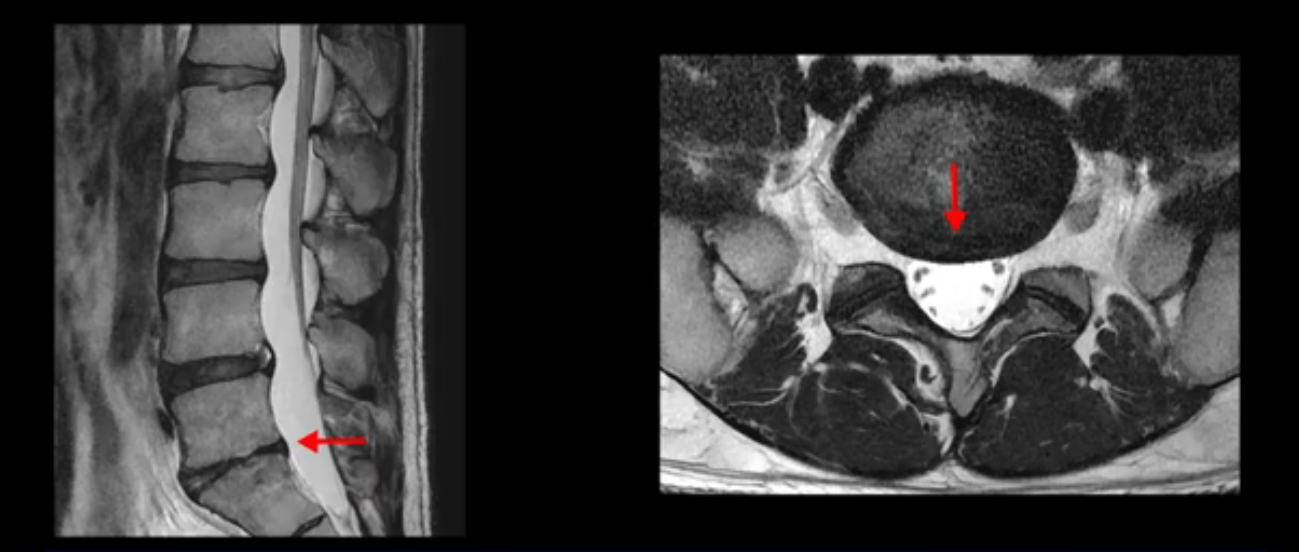

5번 1번 역시 가운데로 디스크 조금 밀려 나와있지만 신경 공간 넓이는 아주 넓어서 신경 눌림 있을 거라고 예상이 안됩니다.

추간공도 보시다시피 왼쪽, 오른쪽 전부 다 매우 넓어서 신경이 눌릴만한 부분이 전혀 보이지 않습니다.

앞서 1번 2번, 4번 5번, 5번 1번의 디스크가 찢어지고 조금 밀려 나온 게 최근에 찢어진 게 아니고 오래된 걸로 보인다고 말씀 드렸죠. 왜 그럴까요? 만약 급성으로 찢어진 것이라면 아주 심한 디스크성 통증이 있겠죠. 기침이나 재채기를 하면 심하게 아프고 허리를 조금만 구부리거나 비틀면 아주 날카로운 통증들이 생길 겁니다. 그런데 이분은 이런 증상이 전혀 아닙니다. 또 디스크의 밀려나온 정도도 전혀 심하지 않기 때문에 이분이 가지고 계신 양쪽 다리 저림, 특히 이분은 누워있을 때도 양쪽 발이 발가락까지 쑤신다고 하는데 이정도 디스크 때문에 그런 증상은 생길 수가 없는 겁니다. 이처럼 이분의 가벼운 디스크 탈출은 이미 오래 전에 진행되었고 섬유륜 자체는 이미 아문 상태인데도 디스크내장증을 진단받은 환자들 중에는 본인이 섬유륜 파열 환자라고 끝까지 믿는 분들이 많습니다. 다시 말하지만 디스크내장증이라는 진단을 받은 환자들을 보면 거의 전부 다 섬유륜 파열 증상이 아닙니다. 증상이 완전히 다릅니다. 진단이 애초에 잘못되면 어떤 치료를 받아도 좋아질 수 없습니다.